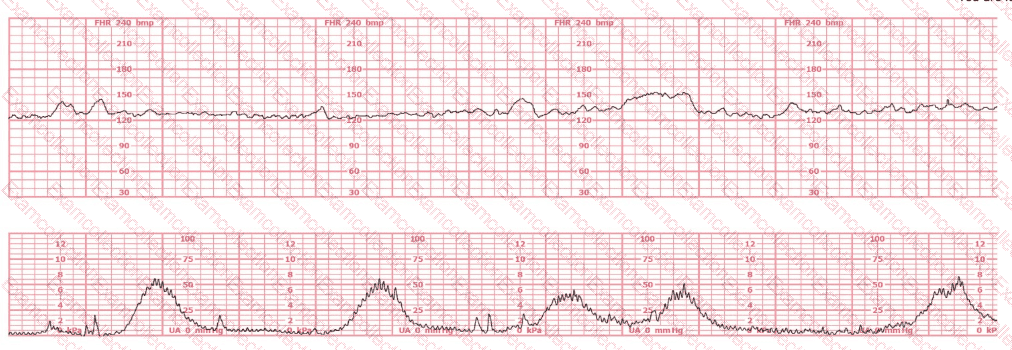

A woman is admitted to labor and delivery with vaginal bleeding. This tracing is obtained. This is most consistent with: